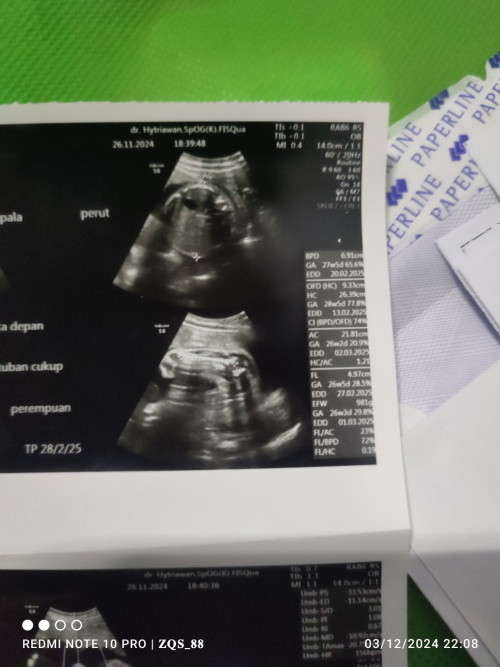

mam cara baca hasil USG gmna sih. liat tinggi badan sama berat badan apa yg 3.37 cm itu tingginya ? apa normal 11w tinggi segitu ? trus beratnya yg mana sih ? kmaren gak dijelasin dokter soal TB dan bbJ cuman dokter bilang janinnya bagus. aktif gerak2. gtu doang

ini gimana cara baca nya yg benar edd nya yg mana GA nya 27wod